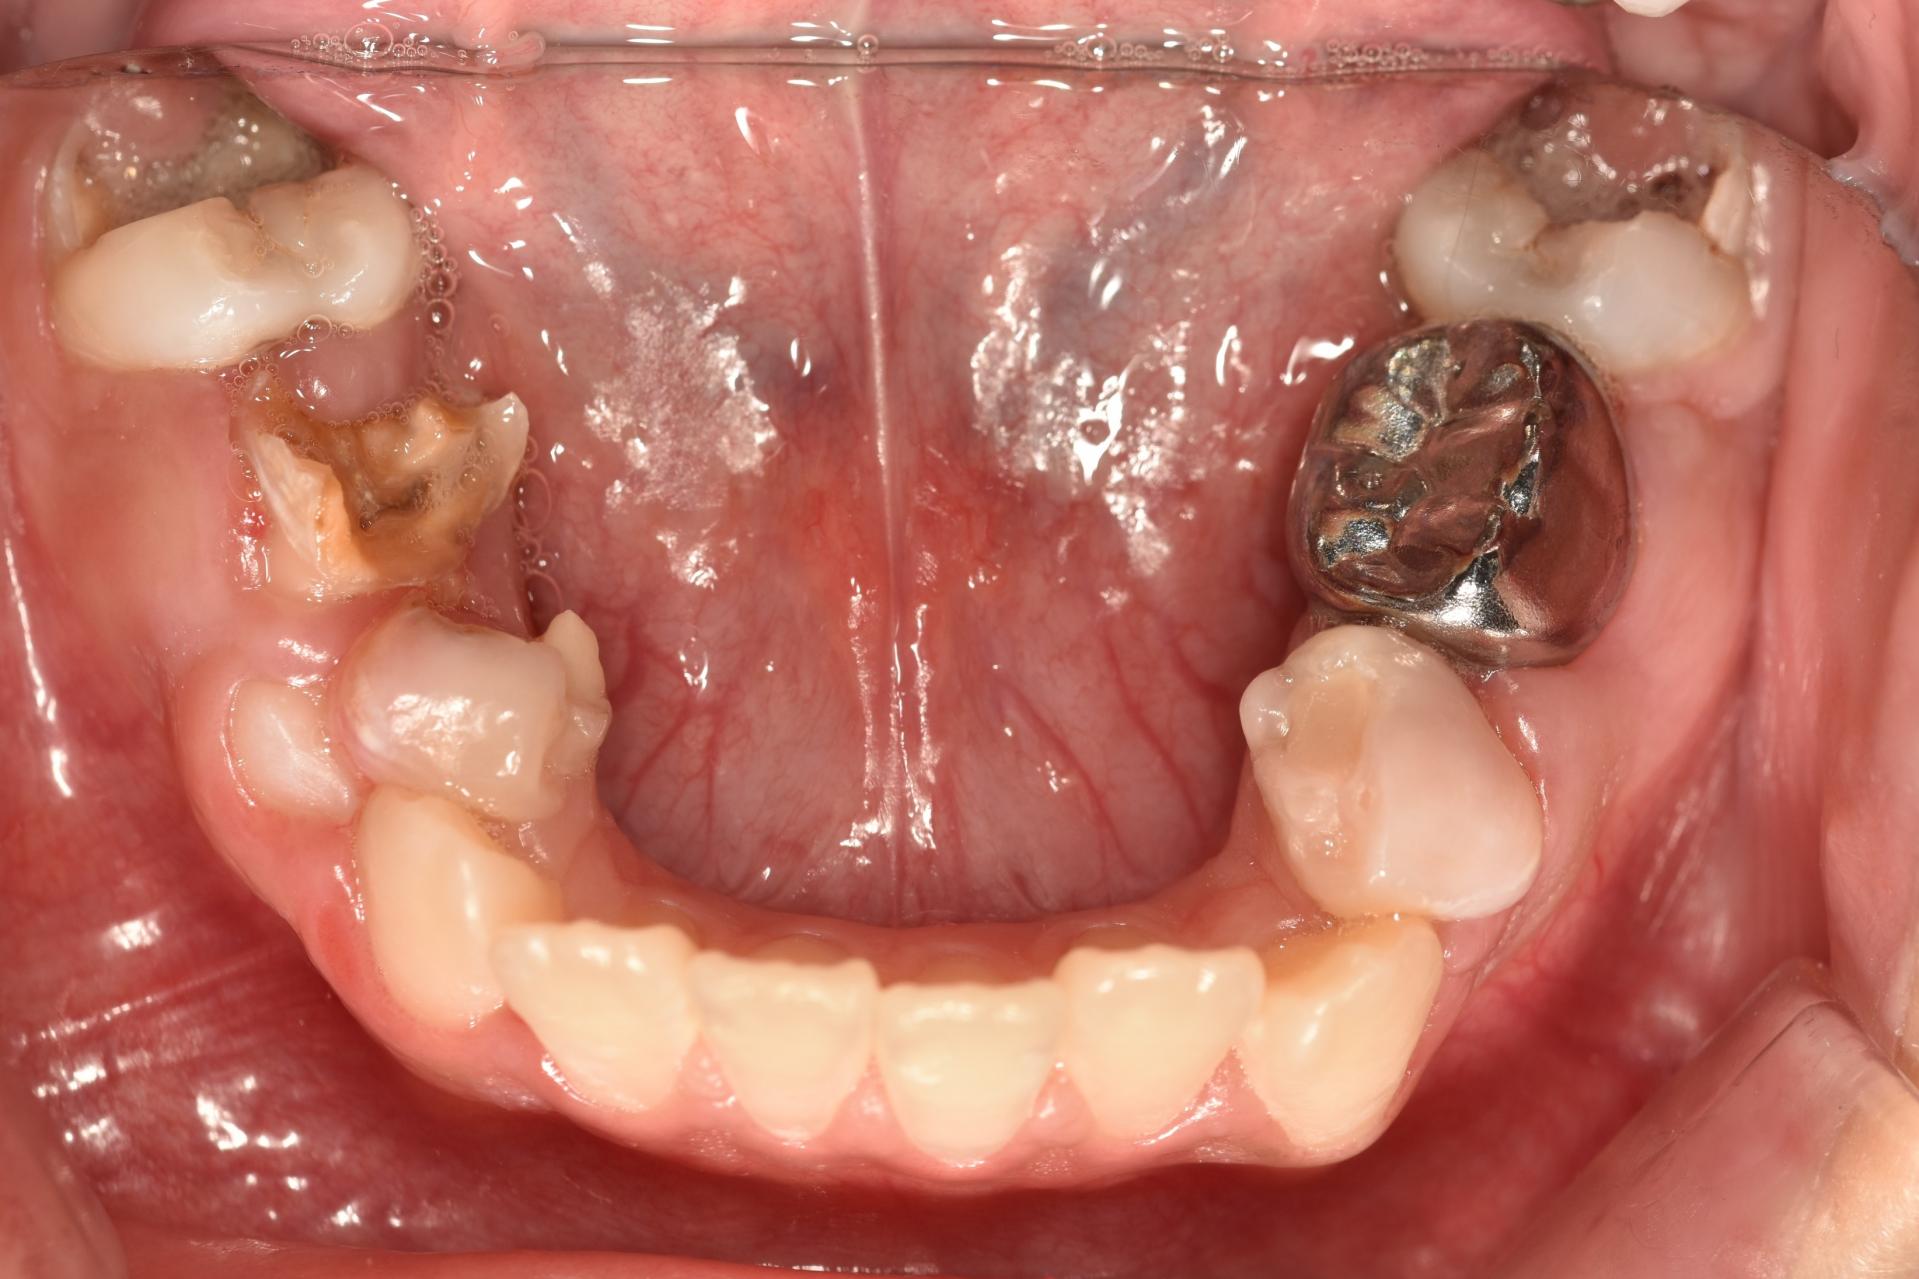

아래치아치료 전 후 입니다.

환아의 치료 전, 엑스레이와 구강 내 사진입니다. 거의 모든 치아에 충치가 있습니다. 특히 아래 어금니는 치아의 절반 넘게 충치로 깨져 없어진 상태입니다. 무서워서 빼야 할 시기를 한참 넘긴 남아있는 유치들도 많습니다. 그리고 영구치 윗니 앞니에 사이 충치가 보이네요.